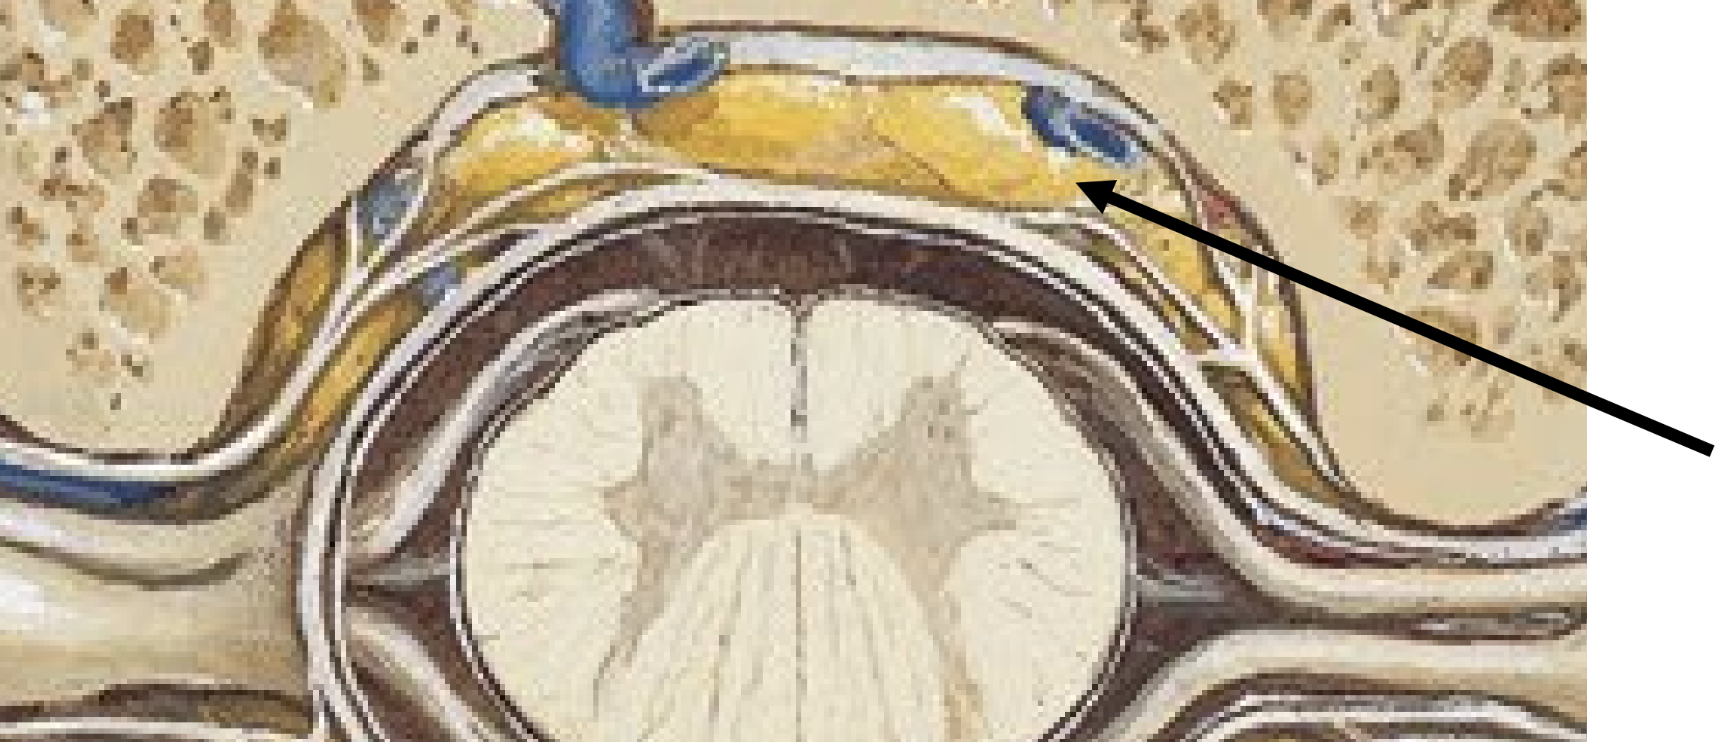

epidural space

• located external to dura mater

• contains fat & blood vessels which supply the spinal cord

<ul><li><p>located external to dura mater</p></li><li><p>contains fat &amp; blood vessels which supply the spinal cord</p></li></ul><p></p>

10

New cards

subdural space

• deep to dura, between dura and arachnoid

• nothing found here normally

<ul><li><p>deep to dura, between dura and arachnoid</p></li><li><p>nothing found here normally</p></li></ul><p></p>

subarachnoid space

located between arachnoid and pia mater

• contains cerebrospinal fluid (csf) — ultrafiltrate of plasma produced in ventricles of the brain

• characteristics: clear, colorless, odorless

• cushions brain

• provides nourishment to and carries waste away from CNS

<p>located between arachnoid and pia mater</p><ul><li><p>contains cerebrospinal fluid (csf) — ultrafiltrate of plasma produced in ventricles of the brain</p></li><li><p>characteristics: clear, colorless, odorless</p></li><li><p>cushions brain</p></li><li><p>provides nourishment to and carries waste away from CNS</p></li></ul><p></p>